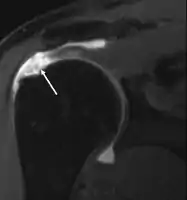

التصوير بالرنين المغناطيسي

التصوير بالرنين المغناطيسي والتصوير باستخدام الامواج فوق الصوتية [24] متماثلان في الفعالية ومفيدان في التشخيص، على الرغم من وجود ننائج إيجابية خاطئة في كليهما بنسبة [15-20%].[25] الرنين المغناطيسي يستطيع بكفاءة اكتشاف اغلب التمزقات الكلية، على الرغم من احتمالية تفويت الصغيرة منها (التي تكون بحجم رأس الدبوس)، في هذه الحالات يستخدم الرنين المغناطيسي مع حقن مادة التباين، الرنين المغناطيسي للمفصل ربما يساعد لتأكيد التشخيص. يجب أن يؤخذ بعين الاعتبار أن الحصول على صورة رنين مغناطيسي طبيعية لا يستثني تماماً التمزقات الصغيرة (نتائج سلبية خاطئة)، بينما لا يستطيع اكتشاف وجود تمزق جزئي كذلك.[26] لكنها تعد حساسة في اكتشاف تآكل الأوتار (أمراض الأوتار) لكن لا تميز بين الوتر المتآكل والوتر الممزق جزئياً. مجدداً الرنين المغناطيسي للمفصل يساعد في التمييز بين الاعتلالات المختلفة [26] بحيث تصل دقته إلى 91% (9% نسبة الخطأ) والتي تعني أن الرنين المغناطيسي للمفصل يعد موثوقاً في اكتشاف التمزقات الجزئية في الكفة المدورة، [26] إلا أنه لا ينصح باستخدامه بشكل روتيني عادةً لأنه يتطلب إدخال حقنة في المفصل مما يزيد من خطورة التعرض للعدوى، وبناءً عليه فإن هذا الفحص يترك للحالات التي يكون فيها التشخيص غير واضح.